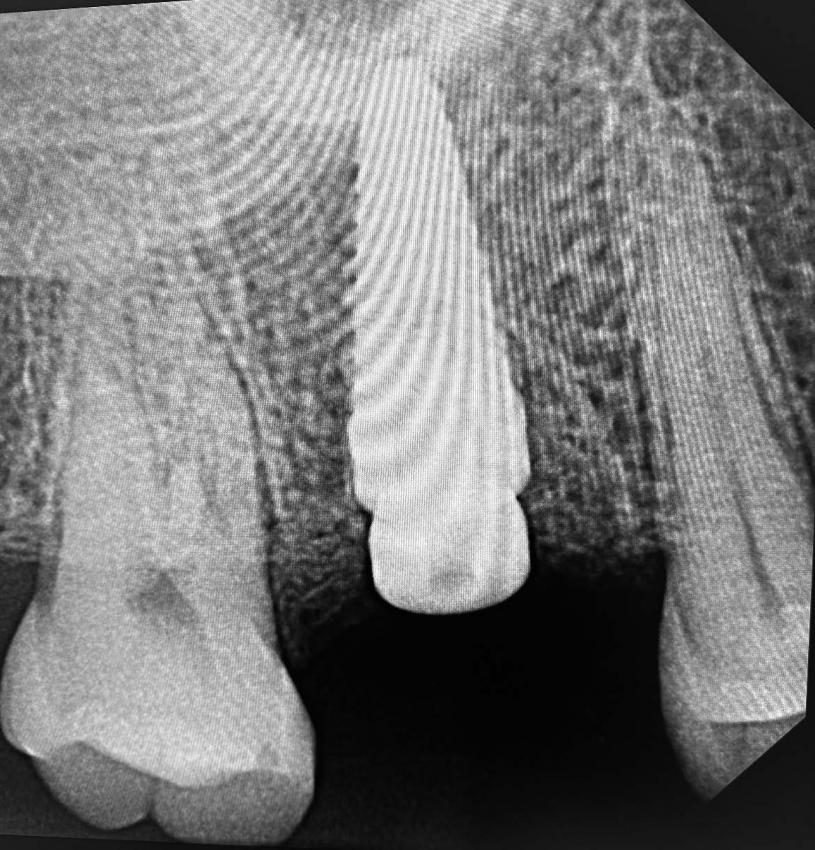

(工商新聞)「Yomi牙科機器人3D導航系統」不但提供精準牙齒及頜骨的重要資訊,可以協助牙醫制定完美的植牙計劃,並幫助牙醫完成該計劃。

Yomi是全球第一也是唯一的植牙機器人,全新科技能確保植牙的準確性,這包括植入物的類型、大小及位置 ;並且減少植牙手術的創傷疼痛、感染風險和快速恢復。

6.斥資引進「YoMi 牙科機器人3D導航系統」,可以拹助牙醫制定完美的植牙計劃,並幫助完成計劃。